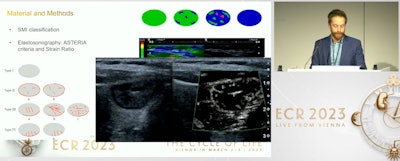

Dr. Davide Negroni presents findings from research he led on combining SMI with elastosonography for diagnosing thyroid lesions. While the method's diagnostic performance was lower than ACR TI-RADS when used in a heterogeneous, it may yield some potential.SMI helps visualize low velocity and microvascular flow by using a clutter suppression algorithm. From there, it provides color overlay images, with previous studies suggesting it can provide additional value over conventional color or power Doppler imaging. Elastography meanwhile measures stiffness of tissues, with harder tissues indicating potential malignancies.

Negroni et al wanted to look at the performance of SMI and elastography in comparison with ACR TI-RADS when it comes to diagnosing thyroid nodules in a heterogeneous population.

They looked at a total of 260 thyroid nodules from 251 consecutive patients with an average age of 58.6 years. The patients presented with at least one thyroid nodule and were candidates for fine-needle aspiration. All identified nodules underwent fine-needle aspiration, and the examination reported a success rate of 86.5% of the sampling. Most of the nodules found were either TI-RADS 3 or 4 (69.2%).

The researchers found that area under the curve (AUC) values favored ACR TI-RADS over SMI, elastography, or combined SMI and elastography.

| Diagnostic performance on thyroid nodules (AUC) | |

| ACR TI-RADS | 0.673 |

| SMI plus elastography | 0.616 |

| SMI | 0.576 |

| Elastography | 0.576 |

By combining all three standalone methods, the AUC improved to 0.699. Additionally, owing to elastography, solid nodules on thyroid findings appear at greater risk of malignancy, Negroni said. He added that no specific vascular patterns at SMI of evolving lesions were identified.